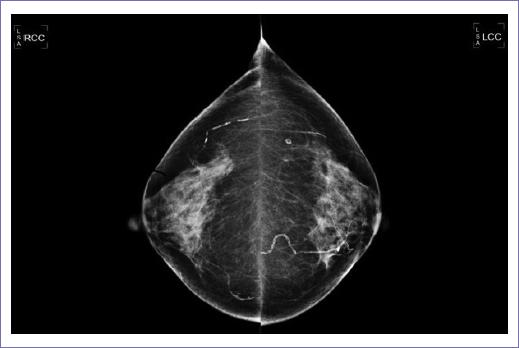

Se continúa con el protocolo diagnóstico mediante panendoscopia y colonoscopia sin reportar alteraciones y/o actividad tumoral (Fig. 3). La mamografía reportó calcificaciones benignas bilaterales y ganglios axilares de morfología inflamatoria; BIRADS (breast imaging reporting and data system) categoría 2 (Fig. 4).

Figura 4 Mamografía en proyección craneocaudal derecha (RCC) y mamografía en proyección craneocaudal izquierda (LCC) que muestran calcificaciones benignas bilaterales, clasificadas como BIRADS (breast imaging reporting and data system) categoría 2.